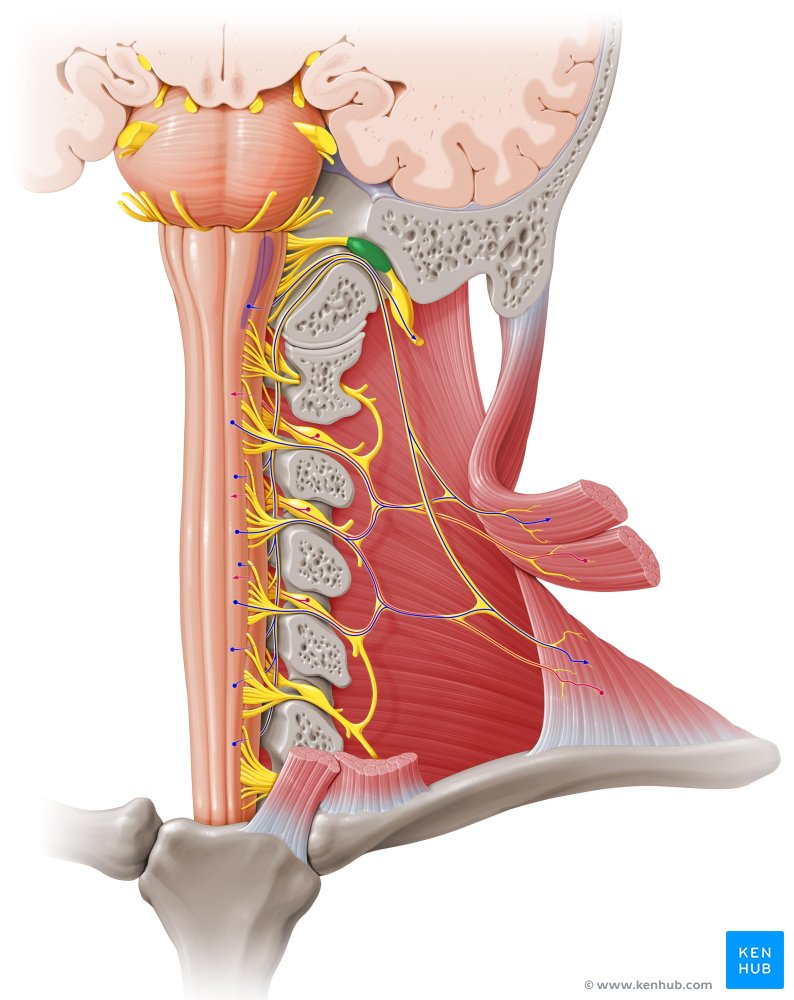

In the Spinal Cord, where is the Grey matter and White matter located

Grey matter is deep (inside), and White matter is superficial

Which spinal cord horns have nuclei associated with sensory information?

Posterior Gray horns

Which spinal cord horns have nuclei associated with motor information?

Anterior gray horns

What is the function of Ascending tracts int he spinal cord?

Carry sensory information

What is the function of descending tracts in the spinal cord

Carry motor muscles from the brain

What does Central Nervous System consist of?

Brain which makes up 97% of the nervous system and Spinal Cord

What is PNS?

Peripheral Nervous System that makes up the network of nerves outside of the brain and the spinal cord.

In the PNS, what are groups of neuron cell bodies called?

Ganglia

In the CNS, what are groups of neuron cell bodies called? (Grey Matter)

Nuclei

In the CNS, what are bundles of axons called? (White Matter)

Tracts or Fibers

In the PNS, what are bundles of axons called?

Nerves